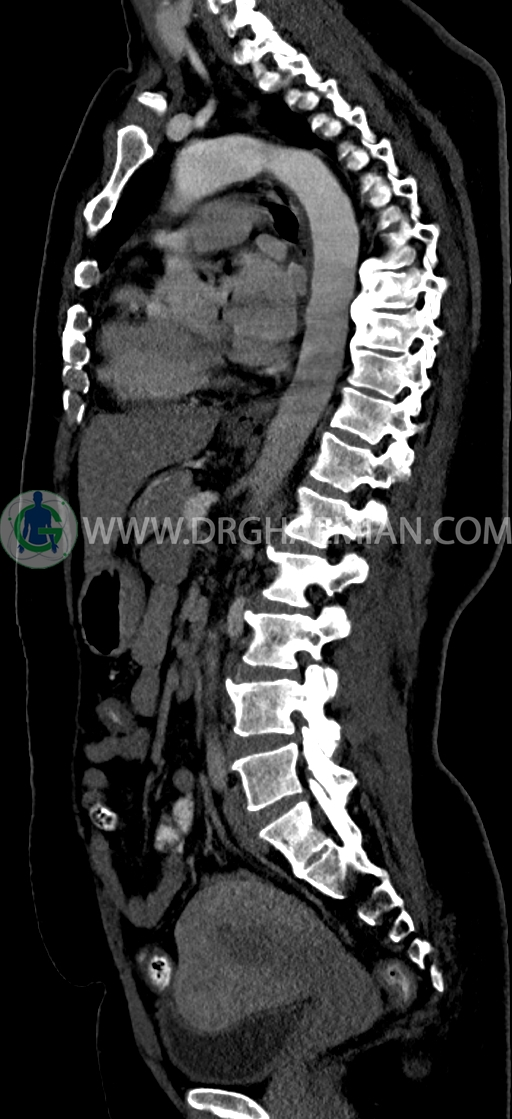

در سي تي اسکن اسپيرال ريه و مدياستن-شکم و لگن با کنتراست خوراکی و وريدی (مولتي ديدکتور 16 با مقاطع ظريف و بازسازي هاي ساژيتال و کرونال) :

–Bridging osteophyte در مهره هاي توراسيک مطرح کننده DISH همراه با کيفوز مشهود است.

–lumbosacral transitional vertebrae